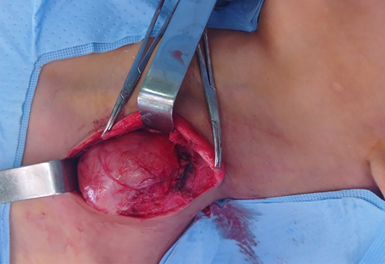

was made to proceed with surgical resection. A lateral cervical incision was

performed posterior to the sternocleidomastoid muscle. The omo-hyoid muscle was

quickly identified after flap dissection. The mass was distant from the

neurovascular bundle and easily dissected from the surrounding structures. A

complete excision was successfully performed (Figures 2 and 3).

Figure 2: The mass was discovered following a lateral cervical

incision made posterior to the sternocleidomastoid muscle

Figure 3:

Excised mass

before being sent for anatomopathological study.